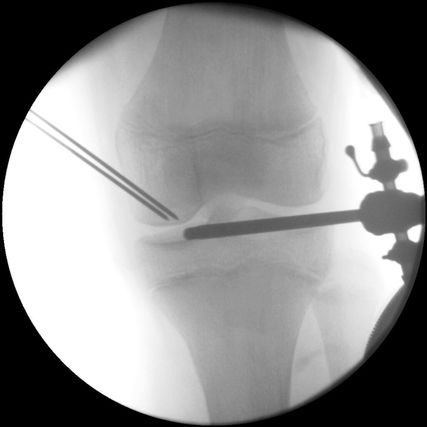

Abb. 3: Arthroskopisch assistierte retrograde Bohrung bei einem 12-jährigen männlichen Patienten mit einer symptomatischen stabilen Osteochondritis-dissecans-Läsion am posterolateralen medialen Femurkondyl

Bei stabilen Läsionen mit intaktem Gelenkknorpel stellt die Anbohrung mittels mehrerer Kirschner-Drähte die chirurgische Behandlungsmethode der Wahl dar. Durch diesen Eingriff soll der sklerotische Rand der Läsion durchbrochen werden, was eine Freisetzung von Wachstumsfaktoren aus der gesunden Spongiosa darunter erlauben und zu einer Verbesserung der Durchblutung führen soll. Dafür kommt sowohl eine antegrade als auch eine retrograde Technik infrage, wobei die retrograde Bohrung den wesentlichen Vorteil bietet, ohne Schädigung der Gelenkoberfläche auszukommen (Abb. 3). Die retrograde Bohrung sollte unter sorgfältiger Bildwandlerkontrolle und unter Schonung der Wachstumsfuge erfolgen.15 Als Unterstützung bietet sich hierfür die Verwendung eines tibialen Kreuzband-Zielgerätes an. Insgesamt ist durch die Anbohrung bei der richtigen Indikationsstellung eine hohe Heilungsrate zu erwarten, wobei eine rezente Studie keinen Unterschied zwischen der antegraden und retrograden Technik feststellen konnte.16